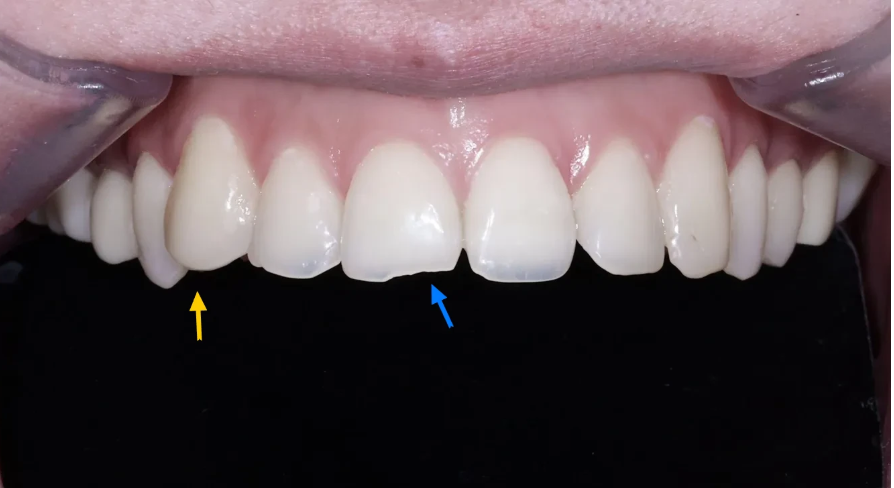

치료 전 - 앞면 관찰

처음 내원하셨을 때 앞에서 본 윗 앞니 상태를 살펴보겠습니다.

초진 사진 - 윗 앞니 끝부분이 비정상적으로 얇아지고 깨져있는 상태

가장 먼저 눈에 띄는 것은 윗 앞니 끝부분(절단면)이 비정상적으로 얇아져 있고, 군데 군데 깨져 있는 상태였습니다. 정상적인 앞니라면 어느 정도 두께가 유지되어야 하는데, 산부식으로 인해 치아가 안쪽에서부터 녹아들어가면서 종잇장처럼 얇아진 것입니다.

초진 사진 - 앞니 끝부분이 불균일하고, 오른쪽 위 송곳니가 돌출되어 있는 모습

절단면이 균일하지 않아서 심미적으로도 상당한 불균형이 보였습니다. 특히 오른쪽 위 송곳니가 다른 치아에 비해 돌출된 형태여서 전체적인 치열의 조화가 깨져 있었습니다.

초진 사진 - 부식으로 앞니가 극도로 얇아진 것이 확인됨

위 사진에서 보시면 부식으로 인해 앞니가 얼마나 얇아졌는지 확실히 확인할 수 있습니다. 전반적으로 치아 색상도 변색되어 있었고, 환자분이 심미적으로 불만족스러워하시는 것이 충분히 이해가 되는 상태였습니다.